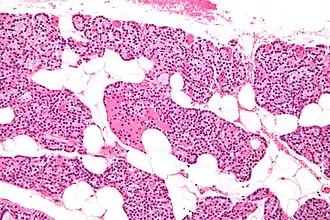

The parathyroid glands are named for their proximity to the thyroid—and serve a completely different role than the thyroid gland. The parathyroid glands are quite easily recognizable from the thyroid as they have densely packed cells, in contrast with the follicular structure of the thyroid.[6] Two unique types of cells are present in the parathyroid gland:

- Chief cells, which synthesize and release parathyroid hormone. These cells are small, and appear dark when loaded with parathyroid hormone, and clear when the hormone has been secreted, or in their resting state.[7]

- Oxyphil cells, which are lighter in appearance and increase in number with age,[7] have an unknown function.[8]

Intermediate magnification micrograph. H&E stain. The white round structures are fat cells. Adipose tissue comprises 25–40% of normal parathyroid gland tissue.[7] -

High magnification micrograph. H&E stain. The small, dark cells are chief cells, which are responsible for secreting parathyroid hormone. The cells with orange/pink staining cytoplasm are oxyphil cells